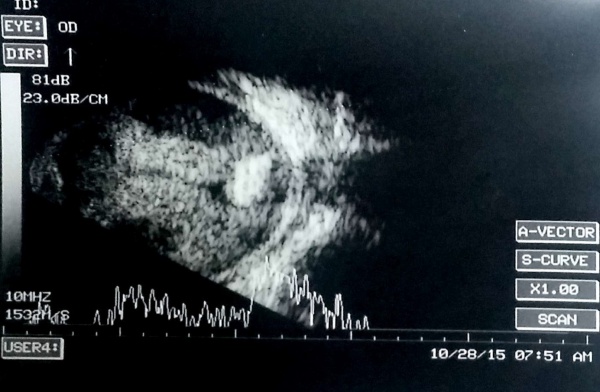

Ultrasonographic appearance of Retinoblastoma

Ocular echogram showing moderate to high amplitude echoes usually with acoustic shadow (calcification) in a child with leukocoria denotes a retinoblastoma unless proven otherwise.